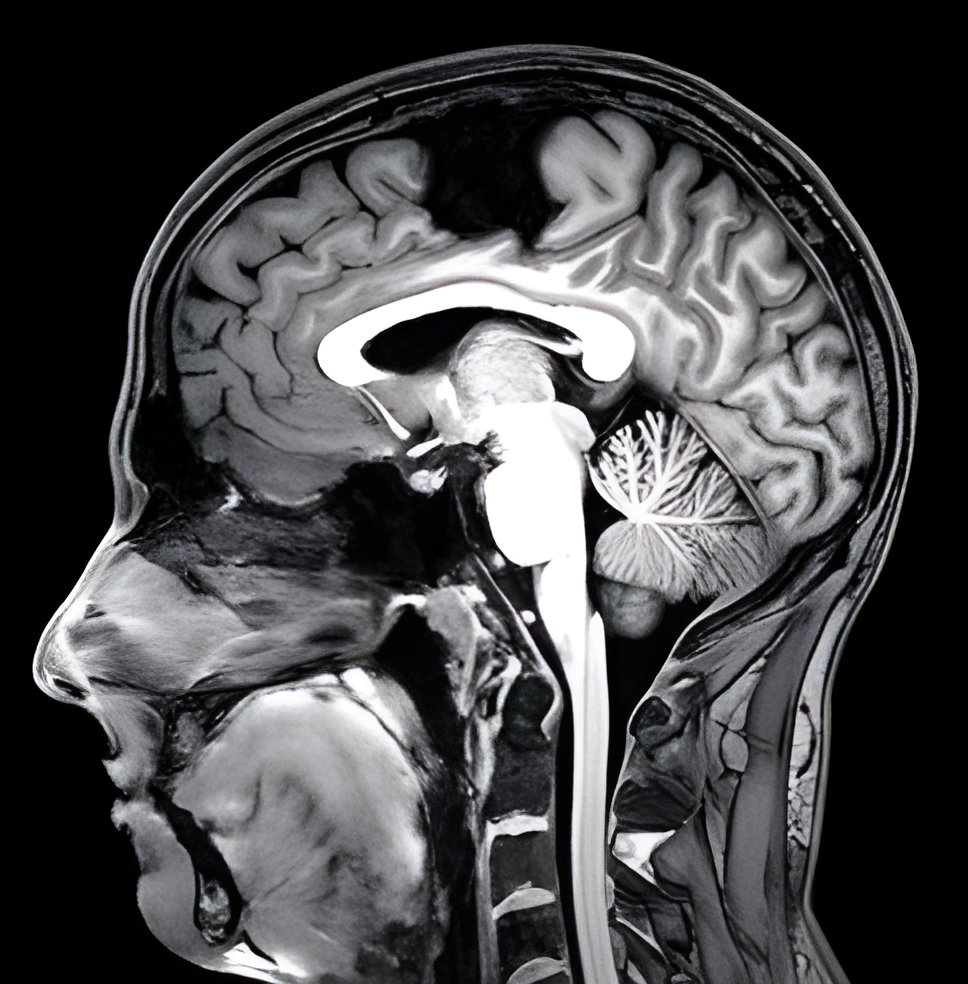

一名死亡SCP-7455-1实例的核磁共振扫描。